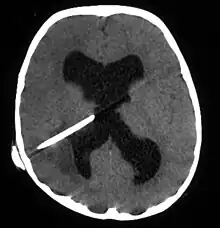

Brain abscess after metastasis treatment.

Anaerobic and microaerophilic cocci and gram-negative and gram-positive anaerobic bacilli are the predominant bacterial isolates. Many brain abscesses are polymicrobial. The predominant organisms include: Staphylococcus aureus, aerobic and anaerobic streptococci (especially Streptococcus intermedius), Bacteroides, Prevotella, and Fusobacterium species, Enterobacteriaceae, Pseudomonas species, and other anaerobes.[5] Less common organisms include: Haemophillus influenzae, Streptococcus pneumoniae and Neisseria meningitidis.[6]